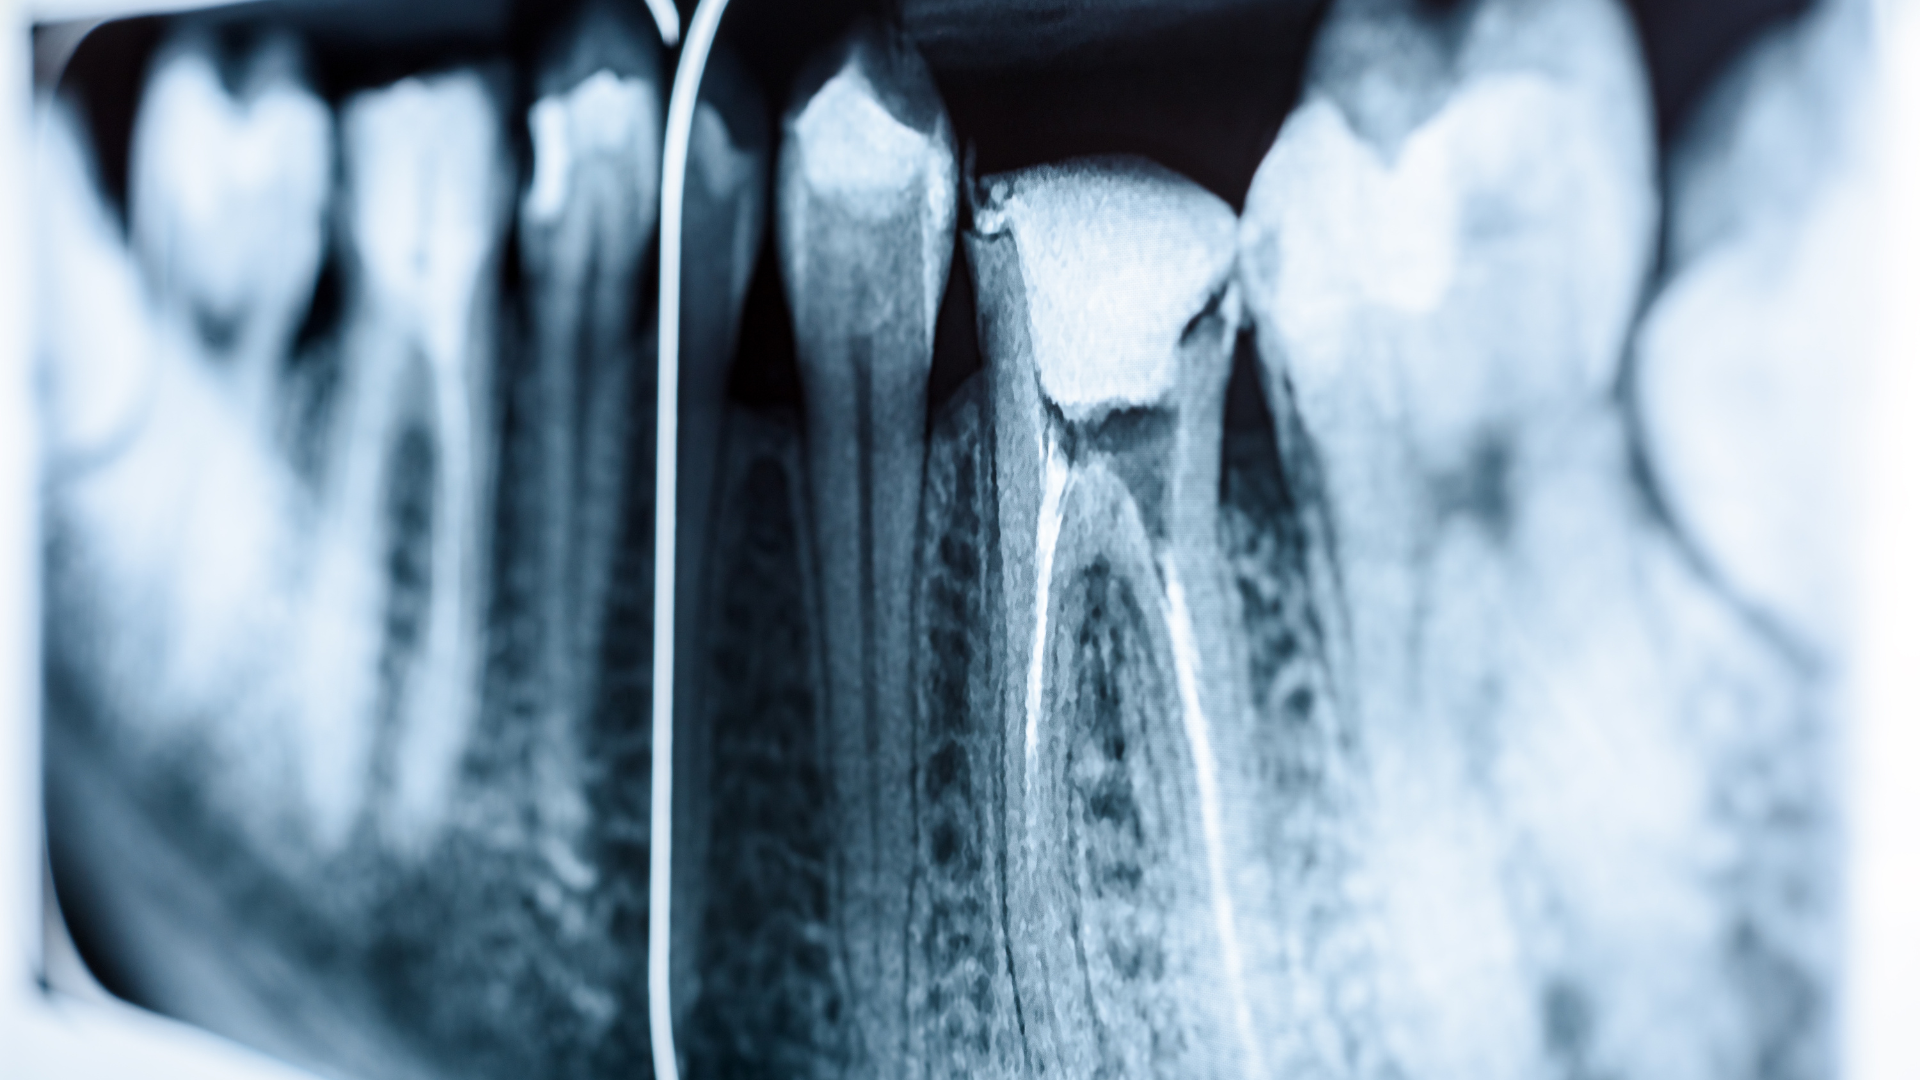

Root Canal Therapy Pike Creek Dental

Root Canal Therapy Pike Creek Dental How To Relieve Pain Before Root Canal Treatment Endodontists and dentists do about 15 million root canals in the united. Web managing root canal pain involves adopting several strategies to alleviate discomfort and promote a smoother. Web a root canal is treatment for infections in tooth pulp, the innermost layer of your teeth. Web if you’ve had a root canal procedure and your gums still hurt, there are. How To Relieve Pain Before Root Canal Treatment.